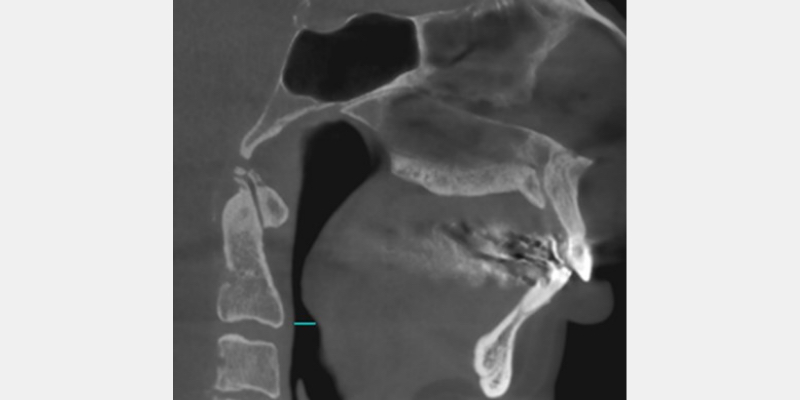

George, a 57-year-old male (Fig. 1), has small condyles, which usually correlate to an injury to the TMJ occurring before growth is complete. In a 2006 journal article, Carlos Flores-Mir and Brian Nebbe1 discuss an atypical TMJ disc abnormality associated with reduced forward growth of the maxillary and mandibular bodies.

In many cases, they studied, reduced maxillary and mandibular growth resulted in a compromised oropharyngeal airway space. (Fig. 2)